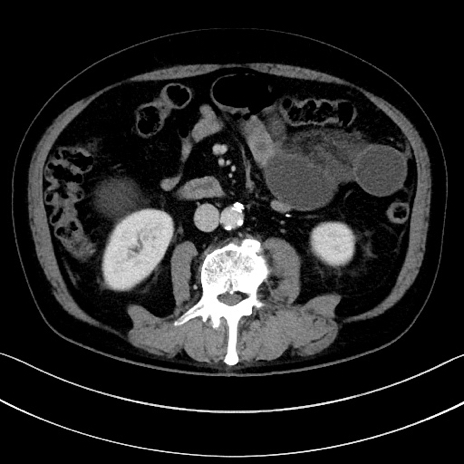

症例15(横断像)

【症例】70歳代男性

【主訴】腹痛

【現病歴】今朝から腹痛あり。全体的に痛い。特に左上の方。排ガスが今日はない。冷や汗が出る。

【既往歴】直腸癌術後

【身体所見】左側腹部〜上腹部に圧痛あり。腹膜刺激症状明らかなではない。軽度反跳痛。左下腹部に術後瘢痕あり。

【データ】WBC 7700、CRP 0.02